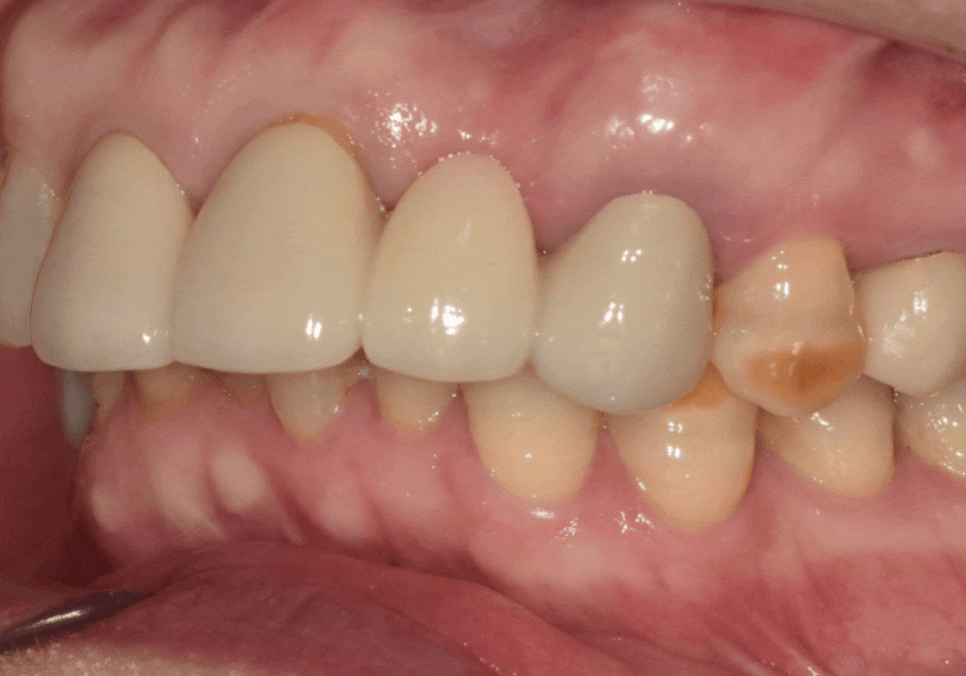

앞니 임플란트는

단순히 튼튼하게 심는 것을 넘어

'옆 치아와 얼마나 자연스럽게 어울리는가'가

생명입니다.

특히 이 환자분처럼 주변 치아도 크라운인 경우,

색상이나 각도가 조금만 어긋나도

매우 어색한 인상을 줄 수 있는데요~

어떠세요? 주변 치아와 조화를 이루며

아주 자연스럽게 마무리된 모습이죠?